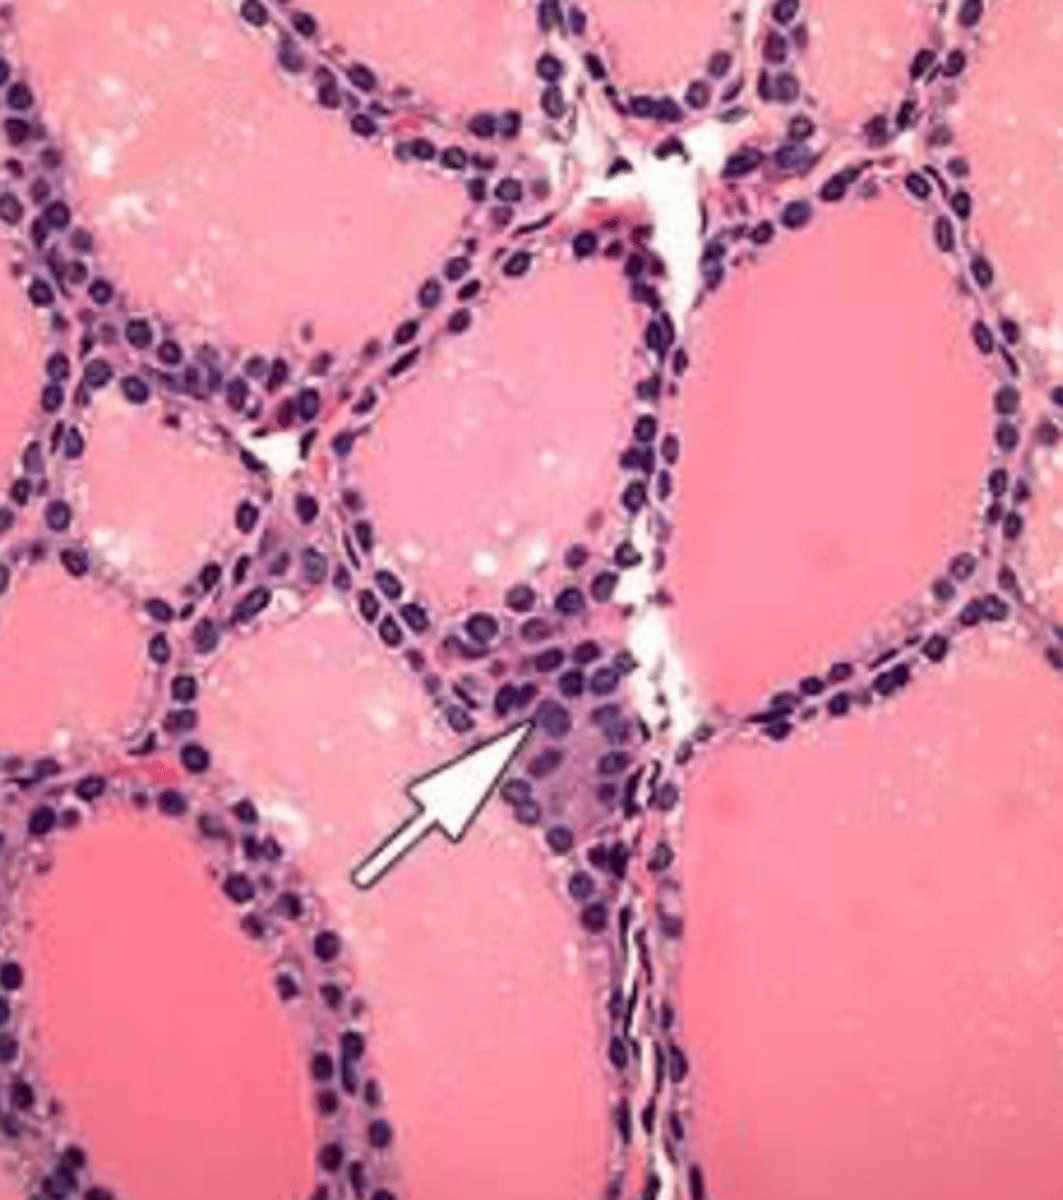

thyroid gland

What structure:

-parenchyma composed of rounded follicles line by simple cuboidal/columnar epithelium , containing gelatinous acidophilic colloid

Thyroglobulin

colloid in thyroid glands contain this, a precursor for active thyroid hormones

Only endocrine gland in which a significant portion of secretory product is stored (outside of cells)

parafollicular C cells

-cells in the thyroid gland found within the basal lamina of follicular epithelium or as clusters; stains less strongly than follicular cells

-secrete calcitonin